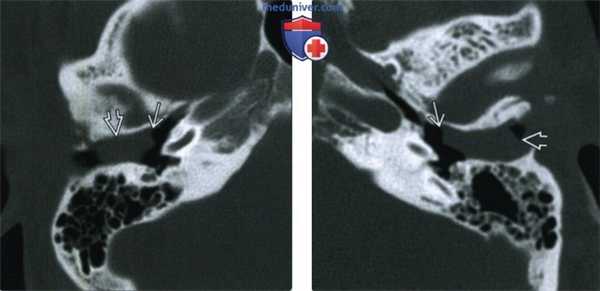

(Слева) При аксиальной КТ в коаном окне у пациента с признаками обструкции НСК, выявленными при отоскопии, в НСК визуализируется мягкотканная «пробка», лежащая снаружи от барабанной перегородки. Обратите внимание на отсутствие изменений костей поблизости.

(Справа) При аксиальной КТ в коаном окне у пациента с кондуктивной тугоухостью в левом НСК снаружи от барабанной перепонки визуализируется мягкотканная пробка, выглядящая доброкачеавенной, достигающая наружного края костной части НСК. Среднее ухо и кости, образующие стенки НСК, не поражены.

2. КТ при обтурирующем кератозе:

• Костная КТ:

о Мягкие ткани, выглядящие доброкачественными, заполняющие НСК:

- Возможно диффузное расширение НСК

- Нет эрозий костей (в отличие от холестеатомы НСК)

о Двухсторонние изменения (50%)

о Среднее ухо интактно, кроме запущенных случаев ОК